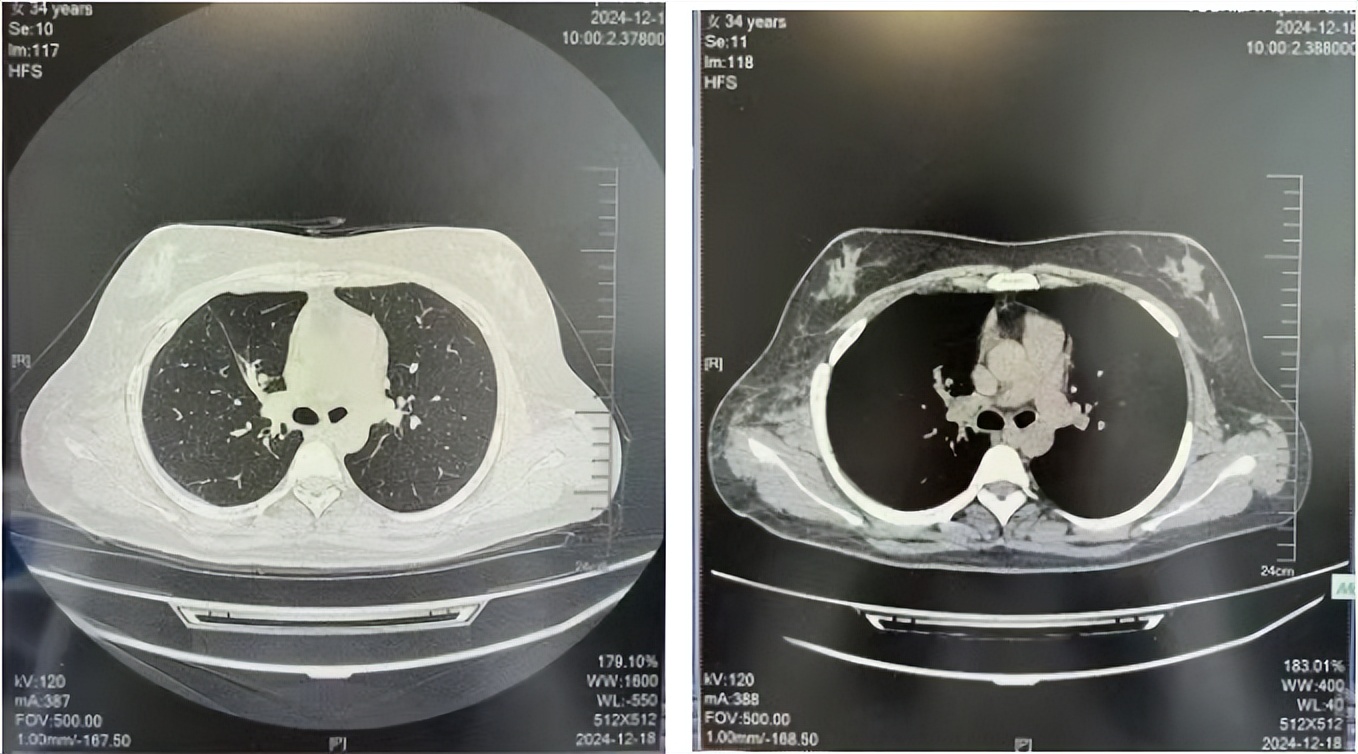

2024.12